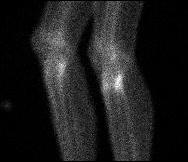

Bone scan

Increased uptake tibial plateau